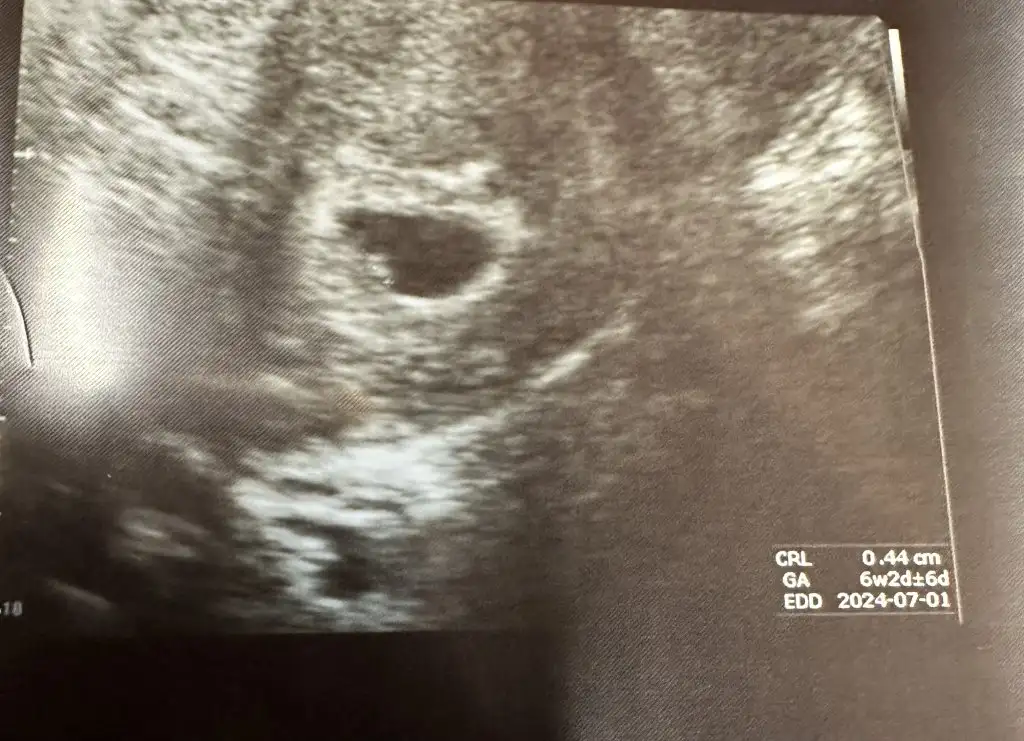

5+5 bizim de😊 6+1de umarim gorulebilir kalp atimi. Hos gerci daha keseyi bile gormedim ben ama🤣

2 Gün önce devlet hastahanesinde doktor kese var bebek yok demişti.2 hafta sonra tekrsr bakalim dedi.bekleyemedim ozele gittim.bebegi de gördük.kalp atışını da duyduk.6+3 dedi doktor.beni de ekler misiniz listeye? 😀